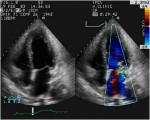

L’ Ecocardiografia rappresenta l’esame diagnostico principale per la diagnosi di insufficienza mitralica. Ci permette infatti la visualizzazione morfologica dell’apparato valvolare e delle camere cardiache, durante tutto il ciclo cardiaco, e quindi ci consente di valutarne lo stato e la funzionalità. Eseguita in prima istanza per via transtoracica (TTE) con la metodica bidimensionale è in grado di chiarire l’etiologia del rigurgito, mentre integrata con le metodiche doppler ci consente di quantificarlo.

L’area del jet di rigurgito, esaminata al color-doppler , è uno dei parametri più usati, soprattutto quando espressa in rapporto all’area dell’atrio sinistro.

Il diagramma mostra la valutazione della severità dell’insufficienza mitralica usando l’approccio transesofageo con vista asse-lungo. La gravità dell’insufficienza mitralica (1-4+) viene stabilita in base alla lunghezza e alla larghezza del flusso di jet nell’atrio sinistro. LA, atrio sinistro.; RV, ventricolo destro; LV, ventricolo sinistro.

ecocardiografia.jpg

Immagine16.jpg